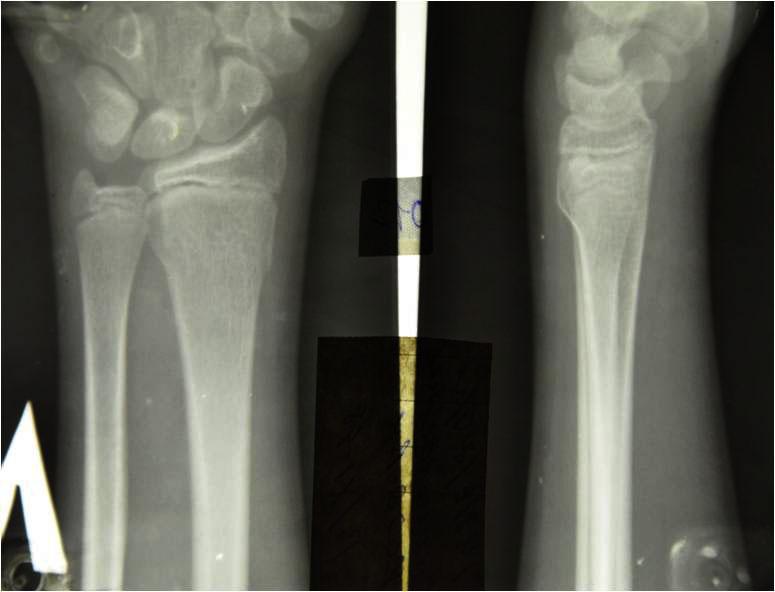

Изображения повреждения костей